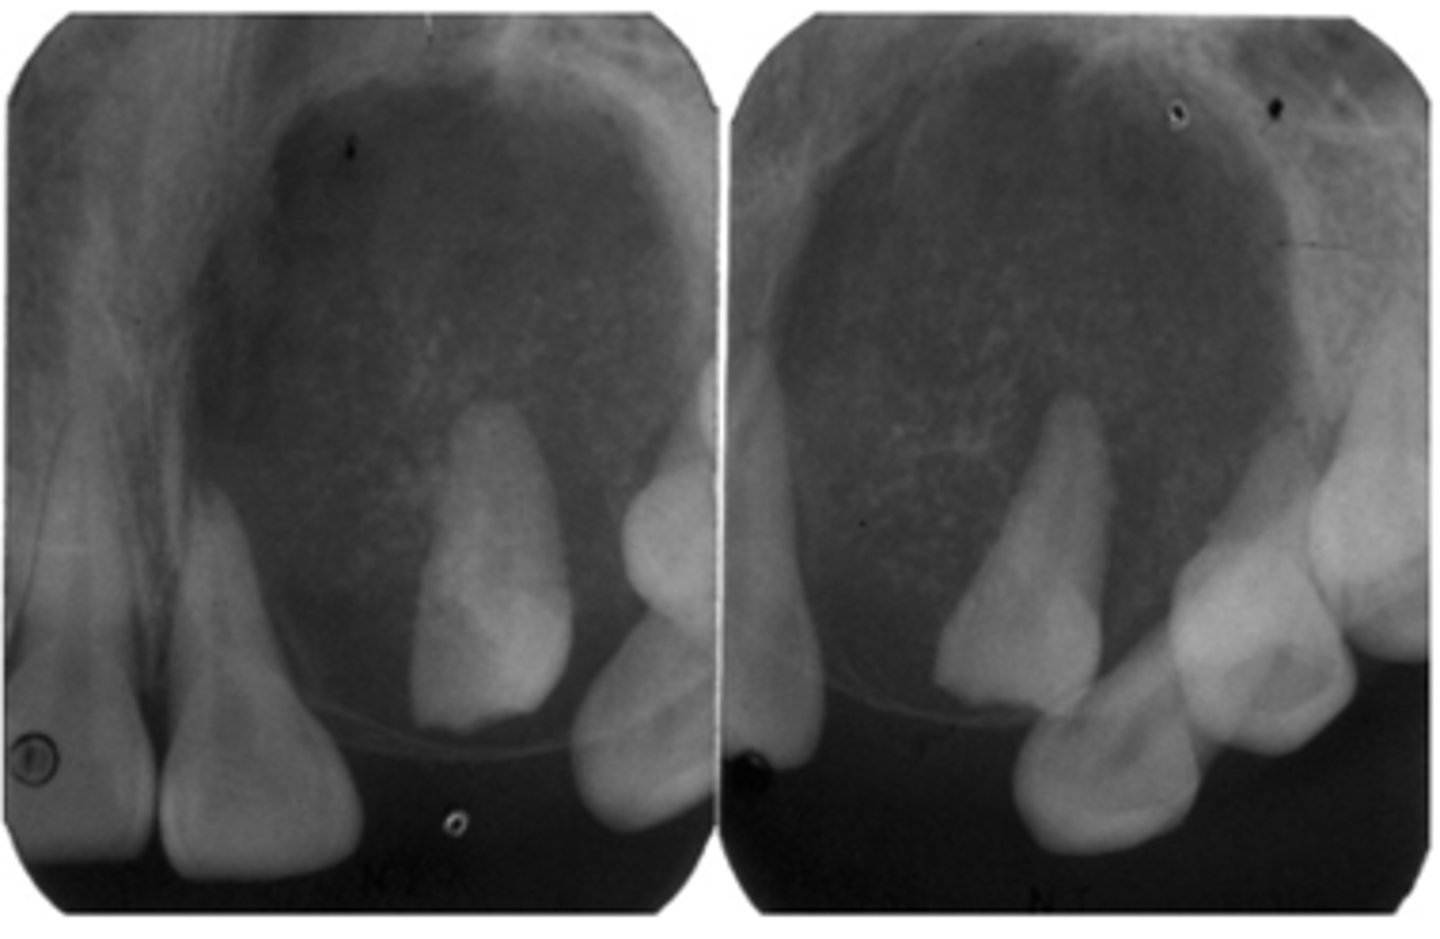

Adenomatoid Odontogenic Tumor (AOT)

20 y/o patient presents with well circumscribed, corticated unilocular lesion on the anterior maxilla that surrounds the entire tooth #6, with mixed radiopacities around the crown of the tooth. The roots of the surrounding teeth are displaced.

What is the diagnosis?

this pathology is associated with unerupted/impacted maxillary anterior teeth and, cortication surrounds the entire tooth and radiopacities surround the crown of the impacted tooth:

ID the pathology:

-Well defined, corticated

-Mixed density (predominantly radiolucent with some radiopacity around crown within)

-Associated with impacted maxillary lateral incisor

-Displacement of adjacent teeth